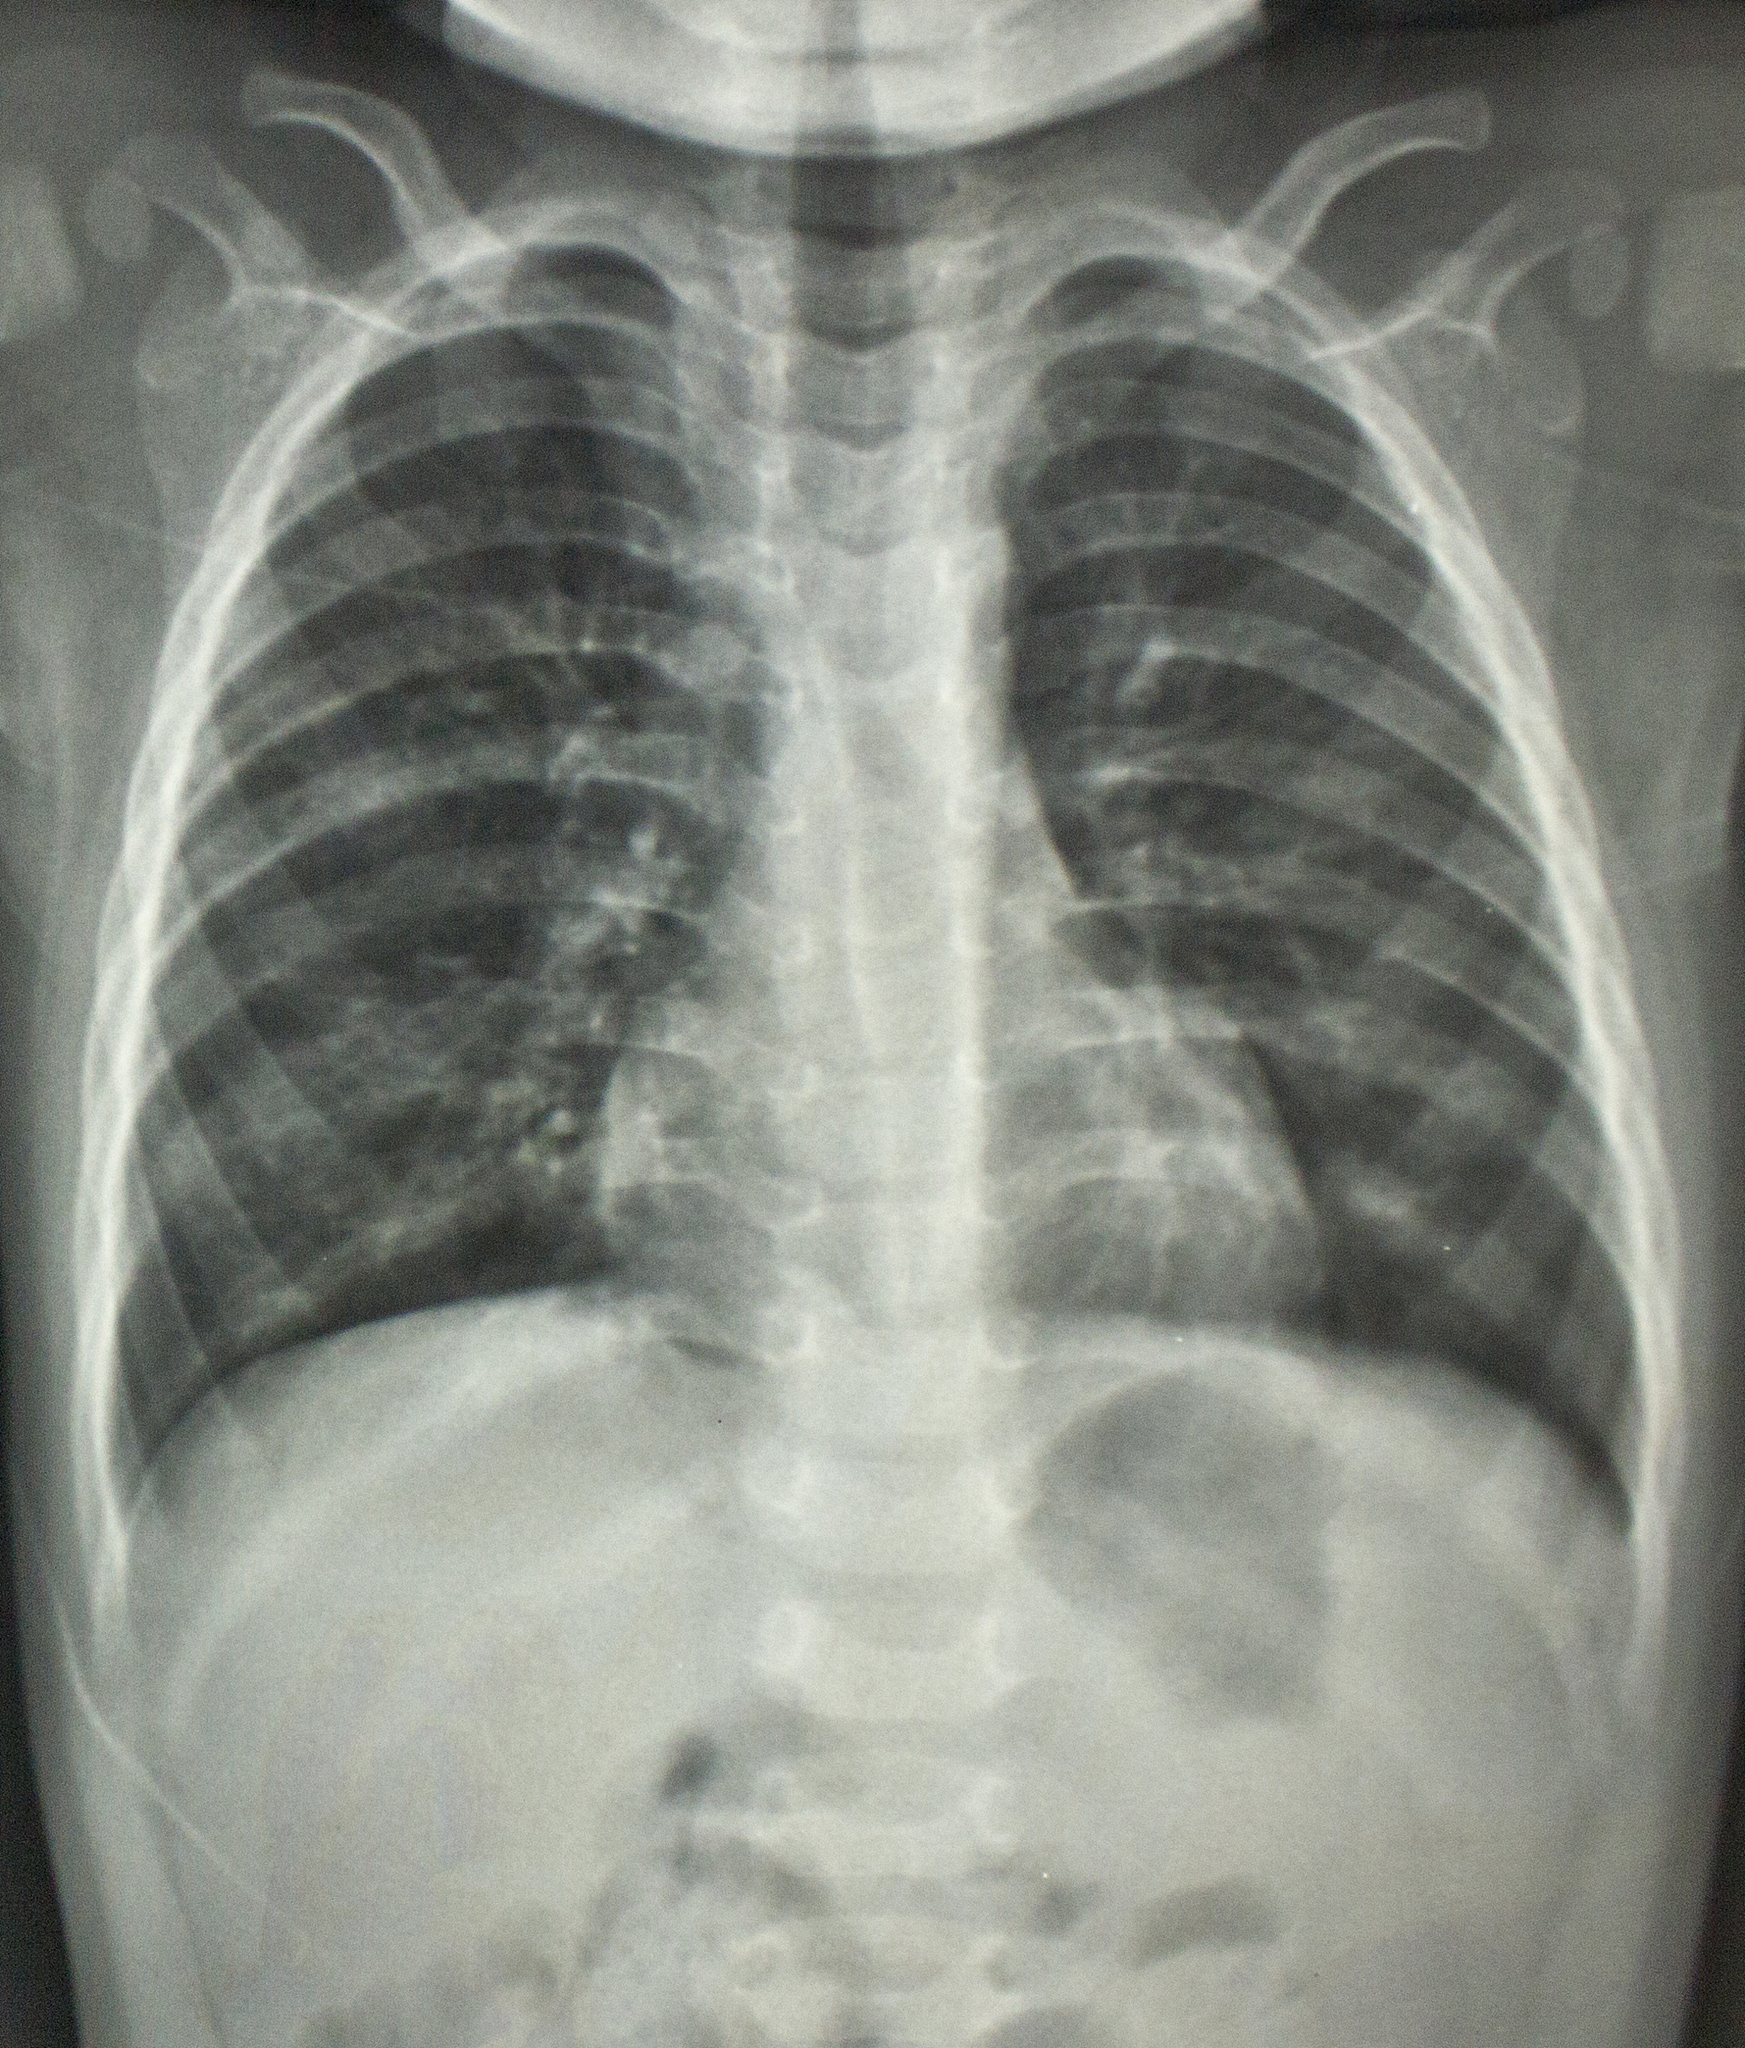

CT 图像灰度与诊断:直接观察靠谱吗?

是的,CT 图像的灰度级代表了不同组织对于 X 射线的吸收系数,因此可以通过直接观察图像的灰度级来进行初步的诊断。但是,专业的医学影像学家需要结合临床病史和其他检查结果等多方面信息,进行综合分析和判断,确定最终的诊断结果。